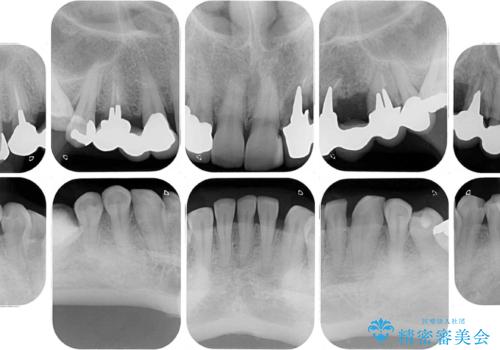

左上の歯は割れてしまっており、抜歯のうえインプラント治療が必要であり、他にも抜歯の必要な歯がある状態でした。

上顎はほぼ全ての歯をセラミッククラウンにて補綴治療を行う必要があるため、気になるデコボコや深い咬み合わせを改善するために下顎と上顎の臼歯部の矯正治療を行うこととしました。

並行して左下にはインプラントを埋入し、矯正治療を終えると同時に補綴治療を行うこととしました。

過蓋咬合(下顎前歯が隠れてしまうほどの深い咬み合わせ)のため、スムーズに歯が動かず矯正治療に時間がかかりましたが、無事に仕上げることができました。